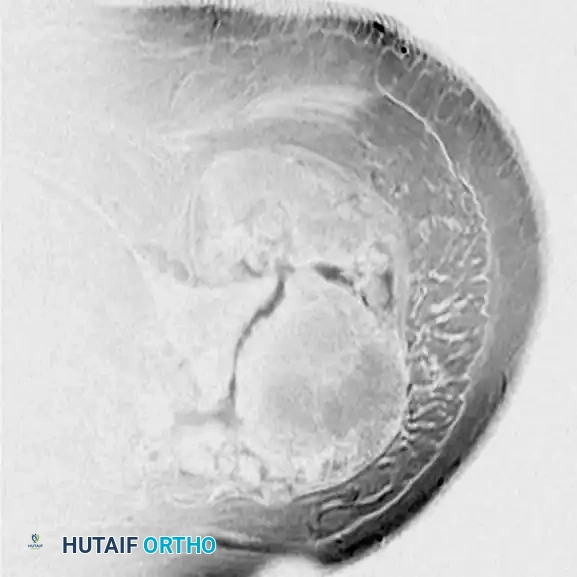

BENIGN TUMORS AND TUMOR-LIKE LESIONS Surgical Diagram

MRI of diffuse PVNS showing characteristic low-signal intensity on T2-weighted images due to profound hemosiderin deposition. Intraoperative view demonstrates the hypertrophic, villous, rust-colored synovium.